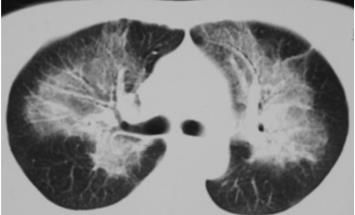

蝶翼征是什么样的?

下图是非常典型的蝶翼征。